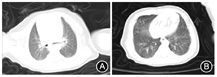

影像学检查:2月5日头颅CT、肝脾及心脏彩色多普勒超声心动图未见异常;但胸部CT提示肺门影无增大,两肺纹理增强,分布均匀,双肺野内可见散在小条状模糊影,见图1。2月10日(入院第6天)床旁胸部X线片提示左下、右上肺少许模糊影,相比入院当天CT,病灶有吸收好转,见图2。

以"新型冠状病毒肺炎""新生儿"为关键词检索截至2020年2月12日中国知网、维普网、万方等相关数据库,未见新生儿确诊COVID-19报道,本例为我国首例新生儿确诊的COVID-19患儿。本例患儿为新生儿期发病,表现为呼吸道和消化道非特异性症状,病程经过较轻,实验室及影像学检查符合COVID-19改变,与已报道儿童病例表现一致[1,2]。影像学显示入院第6天肺部病灶吸收好转,提示若没有明显的呼吸困难等进展症状和血氧饱和度的波动,则选择做床旁胸部X线片复查了解肺部病变,期望减少CT检查可能给新生儿带来的未来伤害。本例患儿父母均为确诊COVID-19患者,家庭聚集传播途径明确。患儿入院第3、4天咽拭子2019-nCoV核酸检测阳性,入院第4、5天肛拭子核酸检测阳性,结合患儿临床表现,提示存在呼吸道和消化道同时感染可能,已有此类相关传播途径报道[3,4]。需警惕在家庭护理中,如喂养等环节,用具消毒不充分及看护人员手卫生不足引起经口传播可能,但也不排除与新生儿长期卧位,呼吸道分泌物下咽有关。患儿入院后进入COVID-19隔离病房治疗,单间隔离,入温箱增加隔离屏障,专职医护人员按三级防护照护,医疗护理操作时严格手卫生和感染防护,定期开窗通风,患儿排泄物和分泌物放入感染专用垃圾袋,并用消毒剂喷洒袋内外表面后入感染专用垃圾桶。因为新生儿感染症状不典型和缺乏相关报道,容易忽视新生儿感染,通过本例新生儿病例,特别提出家庭中需重视新生儿COVID-19的看护及管理问题。针对目前2019-nCoV感染流行情况,家庭成员或密切接触者有疑似或确诊COVID-19时,需警惕新生儿感染可能。因新生儿感染后可能表现为无症状或不典型症状,对新生儿应采用保护性隔离措施,进行专人专护,避免密切接触。在喂养、清洁口腔、更换尿不湿或其他有身体接触行为时,应注意个人防护,加强手卫生,新生儿护理用具用后即进行有效消毒,减少家庭成员间传播。医疗机构应对入院2019-nCoV感染新生儿进行隔离,并减少医务人员流动性。加强病区通风、清洁消毒工作,在基础防护的同时,若进行可能发生体液、分泌物喷射或飞溅,如吸痰、气管插管等工作时,要求加强防护。病区实行封闭式管理,停止一切探视、对家长授课、母乳喂养等行为。需要强调的是,患儿咽拭子病毒核酸检测阴性后仍有肛拭子病毒核酸检测持续阳性,因此不能仅靠咽拭子病毒核酸检测阴性提前解除隔离,建议监测至肛拭子病毒核酸检测阴性。无明显症状新生儿可作为传染源,患儿产生的废弃物、分泌物及排泄物等应做好标记,严格按感染性医疗废物处理。患儿出院后对所在房间及护理单元进行终末消毒。